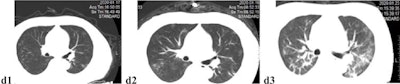

The most frequent CT finding among all patients was ground-glass opacities. Patients with severe disease were more likely to have linear densities, consolidation, "crazy-paving" pattern, white lung appearance, air bronchograms, and pleural effusion.

Patients with severe disease had more lung lobes involved (80% had five lobes involved, compared with 7% of those with mild disease), and their mean total severity scores were higher (11.6 versus two).